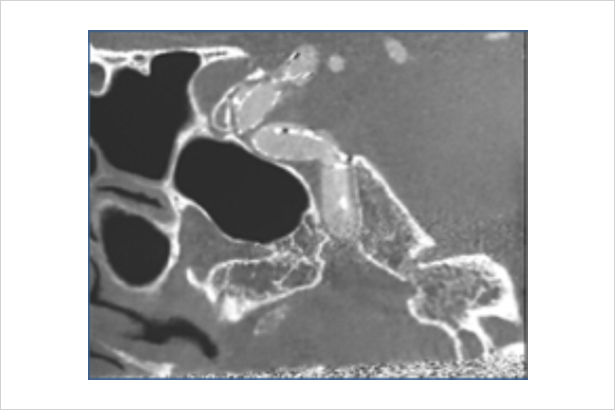

用3D血管重建圖像與實時透視圖像相疊加,并與機架和導管床的機械運動相關聯,追蹤隨動,給醫生在復雜的插管階段以形象化的路徑引導

醫生可在三維圖像上一鍵式選取特定血管

可根據不同部位及臨床觀察重點,提供精細化采集協議(神經/支架/腹部/)